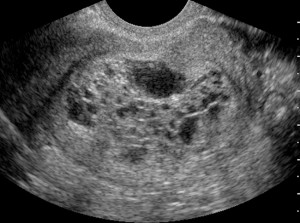

Він може «недоглядіти», прийняти одну «точку» за щось зовсім інше, але! ця точка насправді майбутній дитинка, а зараз - крихітне плодове яйце, серцебиття якого поки не прослуховується, але динаміка розвитку очевидна .

І стверджувати, що вагітність завмерла, можна буде лише в тому випадку, коли невтішні результати ультразвукового дослідження підтвердять ряд аналізів і огляд лікаря-гінеколога.

Багато жінок, які пережили викидень, завмерла вагітність і анембріонія, згадають, що в їх анамнезі теж фігурує 5-6 тиждень від зачаття. Чому так? Відповідь дуже проста. Плодове яйце на цьому терміні розміром з перчинку - 2-5 мм. Воно тільки недавно приліпилося і вагітна жінка про свій стан може ще й не здогадуватися.

Але, побачити його на екрані монітора досвідчений узіст зможе відразу. З діагнозом, правда, не поспішить, відправивши майбутню маму на збереження. Адже головний фактор - серцебиття, на цьому терміні «слабкий» апарат ще не зафіксує. А значить - надія є.

Якщо ж під час ультразвукового дослідження плід нерухомий і серцебиття відсутнє, це вже привід для паніки. Але ще не для направлення на чистку! Тільки після додаткового обстеження на іншому апараті і здачі аналізів.

Якщо ультразвукове дослідження доповнить цей список відсутністю серцебиття, невідповідністю розмірів плода передбачуваному терміну або зовсім «порожнечею» всередині плодового яйця, на жаль, жінку чекає чистка.